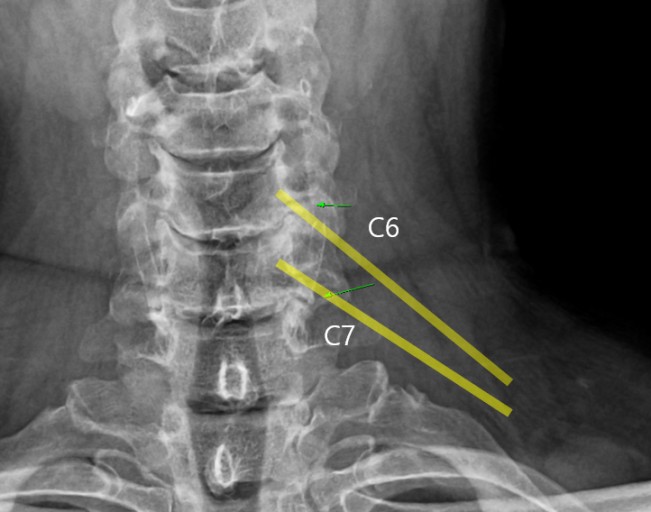

외부로부터 강력한 충격은 주로 교통사고로 인해서 발생돼요. 교통사고만 나면 주로 목을 잡게 되죠? 뒤차에 받혔을 때 주로 경추에 충격을 주어 주로 경추염좌 진단을 받는데 가벼운 증상일 때 빨리 치료를 해야 되므로 입원해서 치료를 받는 게 좋다. 퇴형성으로 목 디스크 증상이 조금씩은 다 있는데 이럴 때 교통사고 나면 전문기관 가서 X-Ray 촬영하다 보면 디스크(경주 염좌) 진단을 받게 됩니다.